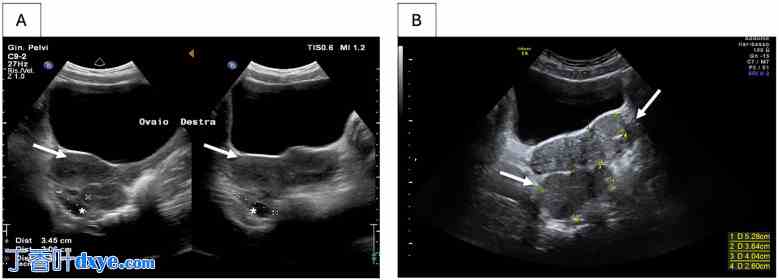

图 1.

盆腔脾脏超声检查。脾脏(A)诊断时和(B)诊断六个月后。白色箭头表示异位脾组织。右侧卵巢以*表示。